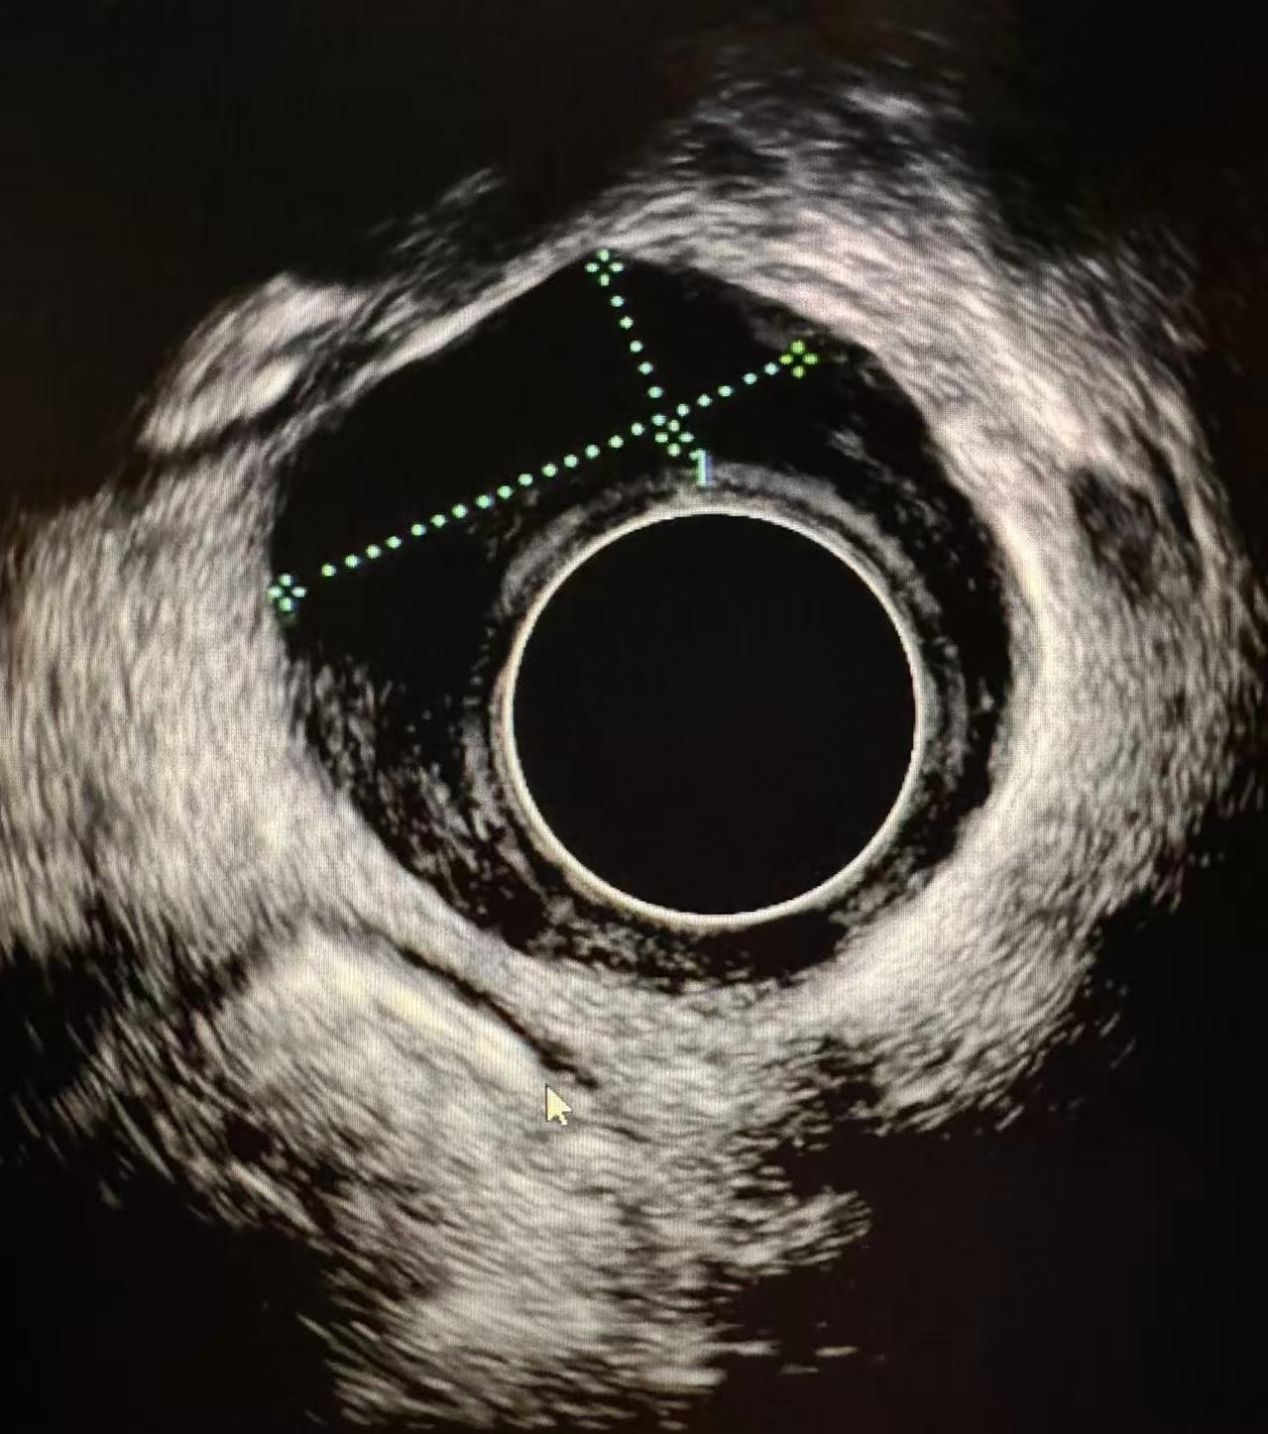

89岁老人确诊食管癌,根治性放疗助力突破生存预期

“感谢你们,让我多活了两年。”近日,91岁的王奶奶来珠江医院复查,各项指标平稳。2年前,换着确诊晚期食管胸上段鳞癌,饱受“吞咽梗阻”的痛苦,在珠江医院放疗科接受新的放化疗法,不仅显著缓解了吞咽困难,更使其生存质量恢复到与正常人无异。2023年,来自四川的王奶奶出现进食后哽咽感,到当地医院检查,胃镜提示:食管距门齿22cm处有一肿物,波及管壁1/3周,食管管腔狭窄。胃镜活…